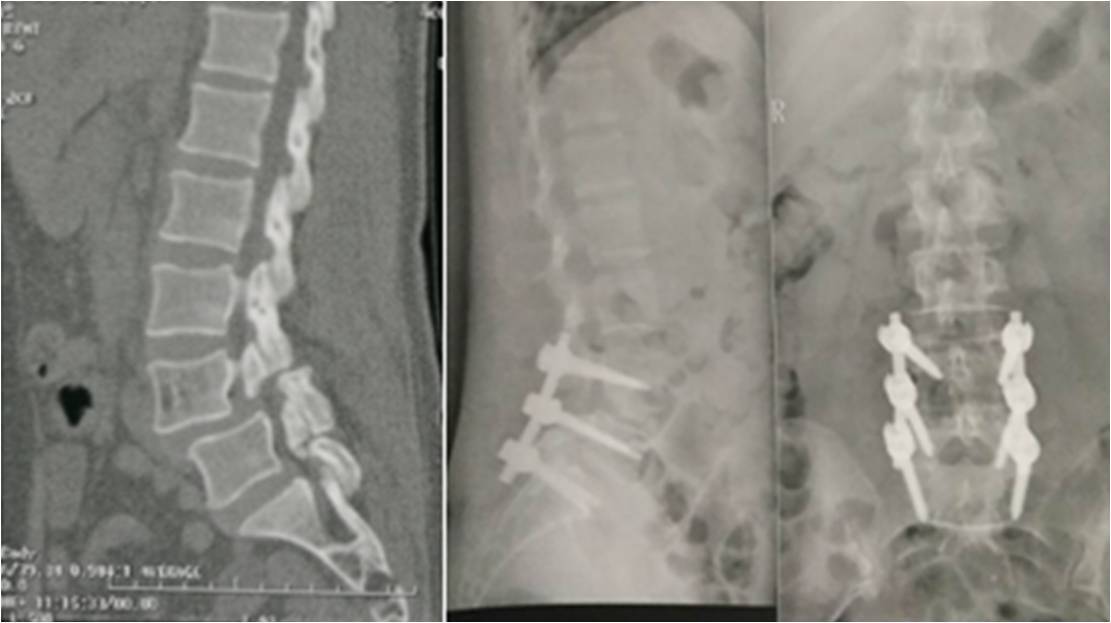

胸椎及腰椎骨折的治療